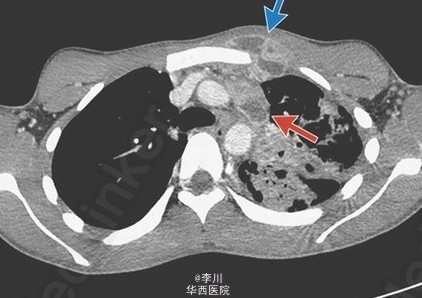

18 岁,男性,既往体健,主因咳嗽 3 月余入院,伴咳淡红色痰、体重下降和发热。近几周其前胸壁出现进展性、局灶性红肿。痰涂片结果为抗酸性染色菌,痰培养结果提示为结核分枝杆菌。HIV 试验呈阴性。患者接受标准抗结核杆菌治疗 8 周,感染仍未控制,表现为红肿加重、皮肤斑疹和皮下脓肿波动。立即给予脓肿切开引流术。逐渐痊愈。Troelsen T, Hilberg O. 2014. Images in clinical medicine. Tuberculous abscess. N Engl J Med. 371(2): 161.